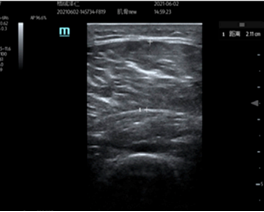

3. Ultrasonography: Cross-sectional areas of the vastus lateralis and lateral head of the gastrocnemius were measured using ultrasonography. Ultrasonography has consistently been reported as a valid tool for skeletal muscle size quantification. vastus lateralis measurements were taken as a direct reflection of muscles benefiting from the exercises performed. Gastrocnemius measurements were taken to investigate potential distal benefits. All ultrasound measurements were performed by the same researcher to enhance reliability [50].

Figure 3. Example of ultrasound measurement of vastus lateralis. The “+” markers indicate the start and end points of the range of measurement.